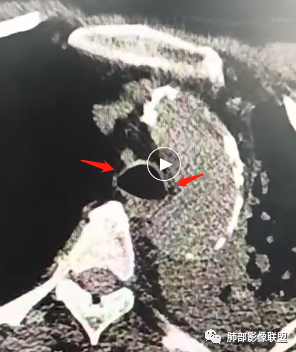

CT表现为仅累及气管的软骨部,局部或弥漫性均匀增厚,可弥漫钙化,后壁常不受累,呼气相横断面面积减少>70%

CT表现气管、支气管壁多发结节样骨、软骨病灶,一般后壁不受累

CT表现气管、支气管管壁不同程度的增厚,气管、支气管内壁单发、多发结节、肿块形成,可发生钙化、骨化,可累及后壁,气管狭窄

CT早期表现缺乏特征,主要为气管、支气管管壁增厚,伴邻近脂肪浸润

常见表现为息肉样腔内肿块,鳞癌常较大,腺样囊性癌最常发生于气管隆突附近,弥漫性气管壁浸润少见。(下图-腺样囊性癌)

CT表现最常累及声门下气管,呈环形增厚,后壁可受累,累及范围较长2-4cm,肺内常多发结节、肿块、实变,易形成空洞

本病例,气管弥漫增厚、没有钙化(肿瘤性病变、支气管淀粉样变性可排除),累及后壁(复发性多软骨炎、气管支气管骨化症排除),周围脂肪间隙清晰(曲霉性气管支气管炎排除),诊断缩小到支气管结核、肉芽肿性多血管炎,左肺实变不张,没有明显结核常有的树芽、纤维灶,患者没有明显结核症状,可以想到肉芽肿性血管炎病伴肺感染、不张可能。